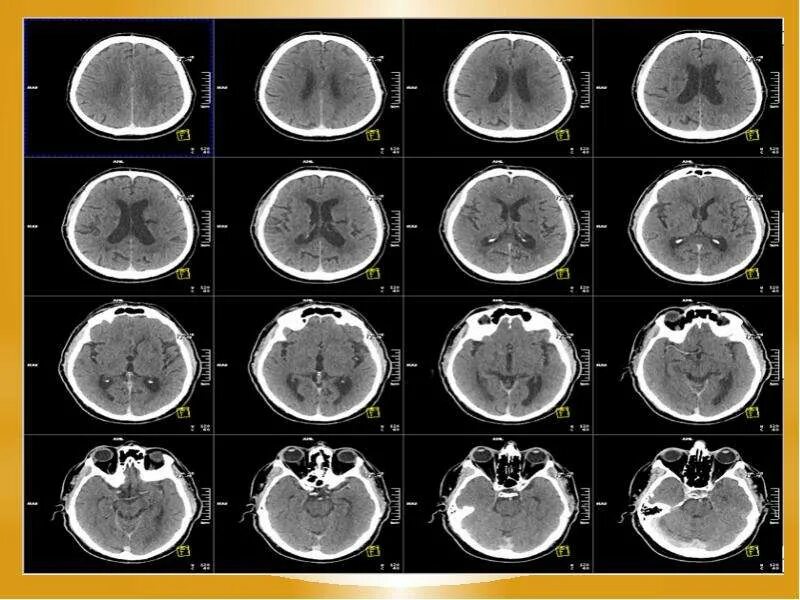

Опасно делать кт